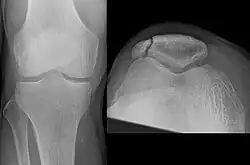

Bipartite patella

Some people have a normal bipartite patella or two-part patella which can appear as a fracture. The fragment is usually seen in the top outer corner of the patella and can be distinguished from a fracture by being present in both knees.[6]